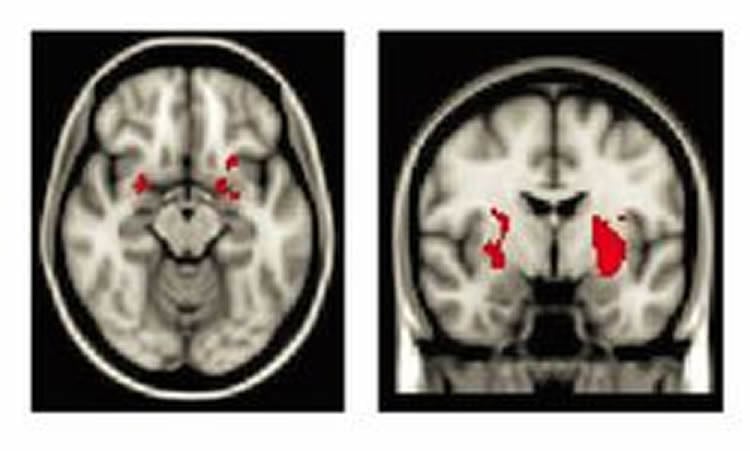

The answer is yes, the researchers concluded. The positive images generated little difference in brain activity between the two groups. But when looking at negative images, the maltreated teens had more activity in brain regions involved in identifying potential threats — including the amygdala, which plays a key role in processing emotions and learning about environmental threats — than the control group. That makes sense, McLaughlin said, since in a chronically dangerous environment the brain is on heightened alert, constantly on the lookout for potential threats.

Again, the two groups were similar in their brain responses to the positive images. But the negative photos caused the maltreated teens’ brains to go into overdrive, drawing more heavily on regions in the prefrontal cortex to tamp down their feelings. The prefrontal cortex is involved in higher-order cognition and integrates information from other areas of the brain to effectively control emotions and behaviors and guide decision-making.

Though it was more difficult for them, the maltreated teens were able to modulate activity in the amygdala just as well as the participants with no history of maltreatment. That suggests that given the right tools, maltreated children may be able to control their emotional responses to real-world situations.

Maltreated adolescents exhibited heightened response in multiple nodes of the salience network, including amygdala, putamen, and anterior insula, to negative relative to neutral stimuli. During attempts to decrease responses to negative stimuli relative to passive viewing, maltreatment was associated with greater recruitment of superior frontal gyrus, dorsal anterior cingulate cortex, and frontal pole; adolescents with and without maltreatment down-regulated amygdala response to a similar degree. No associations were observed between maltreatment and neural response to positive emotional stimuli during passive viewing or effortful regulation.

Child maltreatment heightens the salience of negative emotional stimuli. Although maltreated adolescents modulate amygdala responses to negative cues to a degree similar to that of non-maltreated youths, they use regions involved in effortful control to a greater degree to do so, potentially because greater effort is required to modulate heightened amygdala responses. These findings are promising, given the centrality of cognitive restructuring in trauma-focused treatments for children.